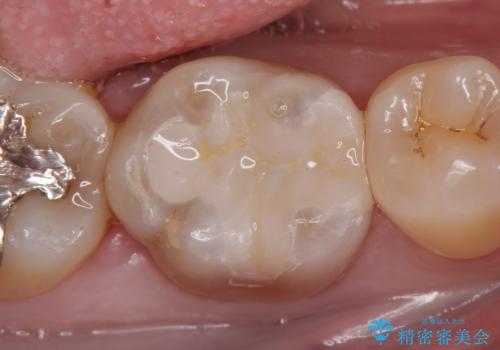

根管治療専門の医院にて処置後、被せもののの製作依頼で来院されました。土台の歯の高さがあまりに低く、しかも周りには粘膜しかない状態でした。このままではペラペラな被せものしか作れず、長期的な予後は見込めません。

歯冠長延長術と角化歯肉の移植を行い、土台の歯に十分な高さを与えると共に周囲に丈夫な歯ぐきを整え、より長期にわたって使っていけるブリッジを製作することができました。

被せものの種類:高透過フルジルコニア ベレッツァ